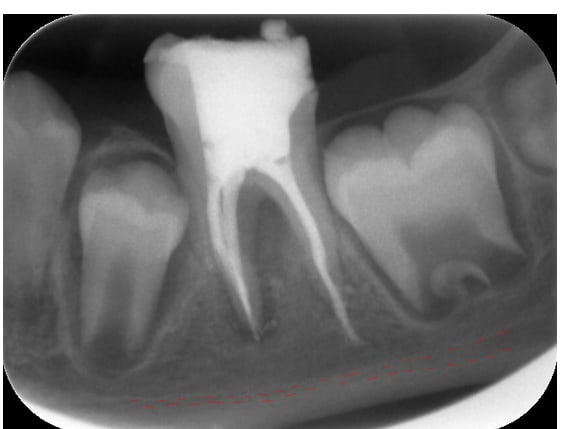

J'obture au Mac Spadden et je fais la radio post op: dépassement sur le canal distal, jusqu'au nerf alvéolaire inf !

Voici des radios:

Post op 1 qinen3 - Eugenol

Par ailleurs il faut se méfier des rx en 2D il n'est absolument pas sur que ce soit dans le même plan que le N.A.I.

Au risque de dire moi aussi une ânerie, je pense que tu es loin du canal. Si la pate part dans le canal, elle s'étend horizontalement comme l'a dit Piccalilly.

En effet Belette, celle-ci c'est la radio post op du jour de l'endo. Ce jour là je me suis dit la même chose. La deuxième radio post op a été prise à J+3 et en distalant l'angle d'incidence du cône radio. Donc ce qu'on voit sur la deuxième radio ne correspond pas à une incidene orthogonale.